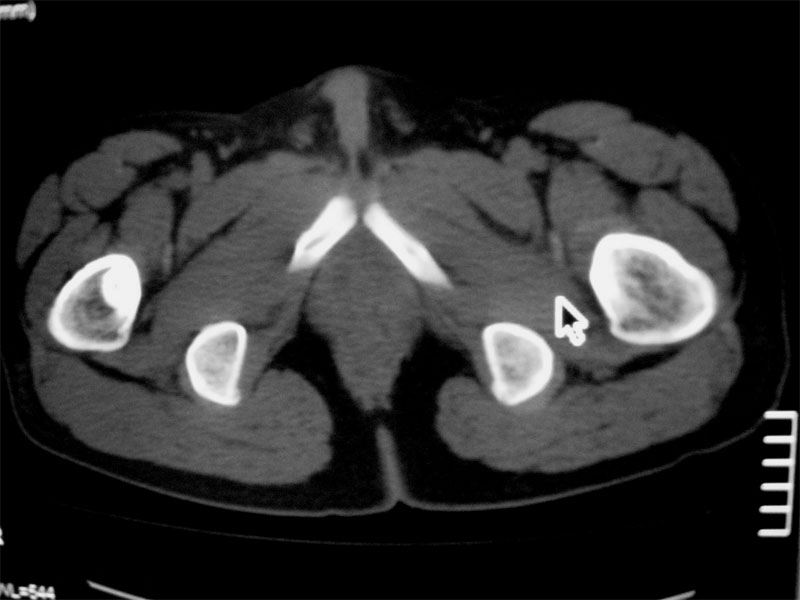

左侧髋关节少量积液.上传骨窗

左侧股骨头坏死,左侧髋关节少量积液

双侧股骨头坏死!!

考虑左侧股骨头坏死。

考虑左股骨头缺血性坏死;右股骨上段良性骨肿瘤,考虑成软骨细胞瘤可能。建议上传骨窗。